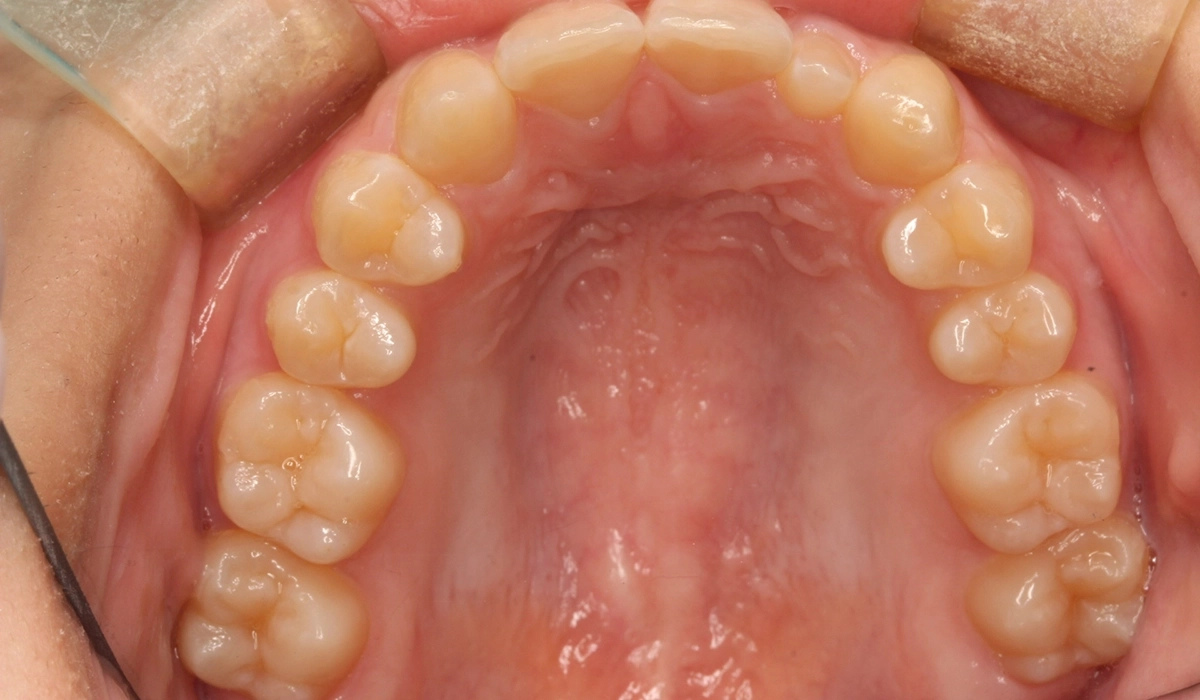

術前:上顎

術後:上顎

今回ご紹介する患者様は、上顎の歯並びのがたつきを気にされており、矯正検査後Ⅰ級叢生と診断いたしました。矮小歯があるため個性を生かして配列。

| 治療内容 | 上顎の歯並びのがたつきを気にされており、矯正検査後Ⅰ級叢生と診断。矮小歯があるため個性を生かして配列。 |